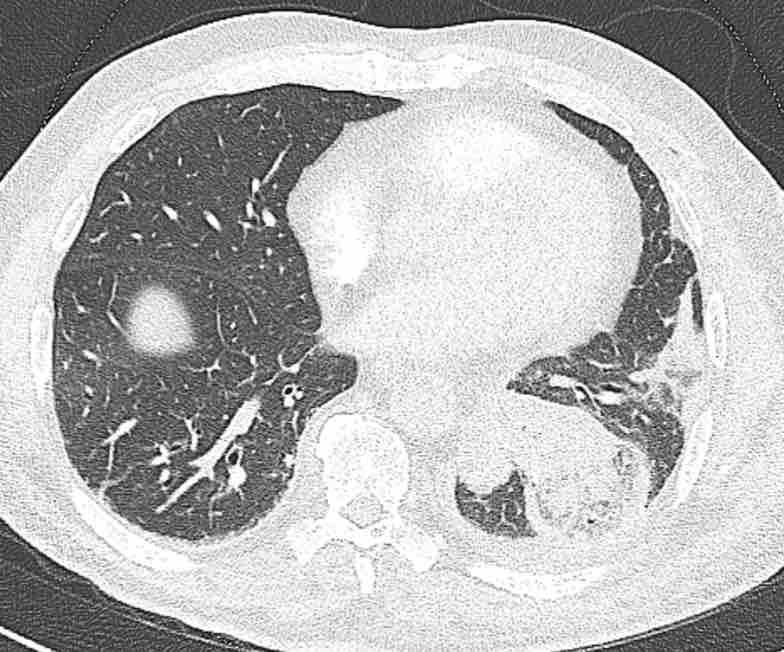

Hình ảnh

Cuộn qua các hình ảnh.

Theo dõi các phế quản của thùy dưới phổi trái cho thấy nhánh phân thùy đầu tiên của thùy dưới phổi trái còn thông; đó là phế quản phân thùy đỉnh.

Các ghim phẫu thuật nằm tại vị trí của các phân thùy đáy sau và đáy bên (LB9/10), vốn thường được cắt bỏ cùng nhau.

Do đó, phân thùy phổi có hình ảnh kính mờ và đông đặc phải là phân thùy đáy trước của thùy dưới phổi trái (LB8).